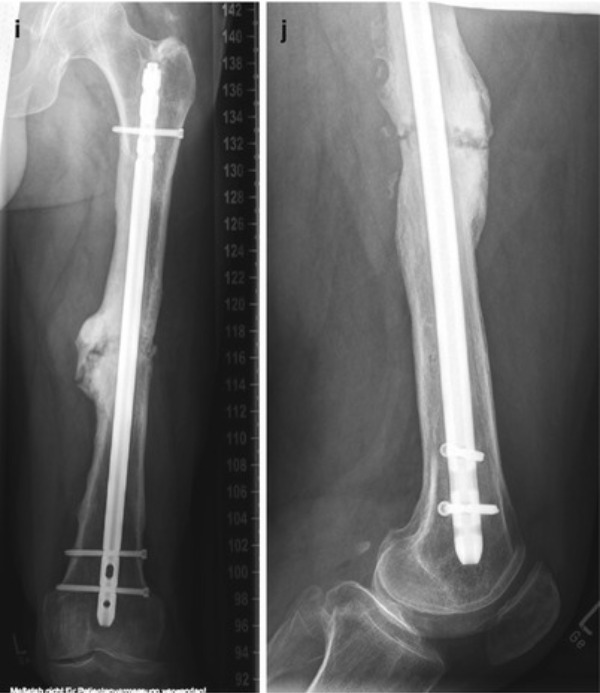

Non-Union Surgery in Jaipur for Proper Bone Healing

When a fractured bone fails to heal even after sufficient time, it is known as a non-union. Non-Union Surgery is designed to restore proper bone healing and stability through specialised orthopaedic intervention. At The Derma Joint Co in Jaipur, this condition is treated with a structured and patient-specific approach.

With the expertise of Dr. Vijay Pilaniya, non-union cases are carefully assessed to identify factors such as poor blood supply, infection, or inadequate fixation. Surgical treatment focuses on stabilising the bone, stimulating healing, and correcting previous complications that prevented recovery.

Advanced fixation techniques and biological support help encourage bone regeneration over time. With proper post-operative care and rehabilitation, patients can gradually regain strength and function.